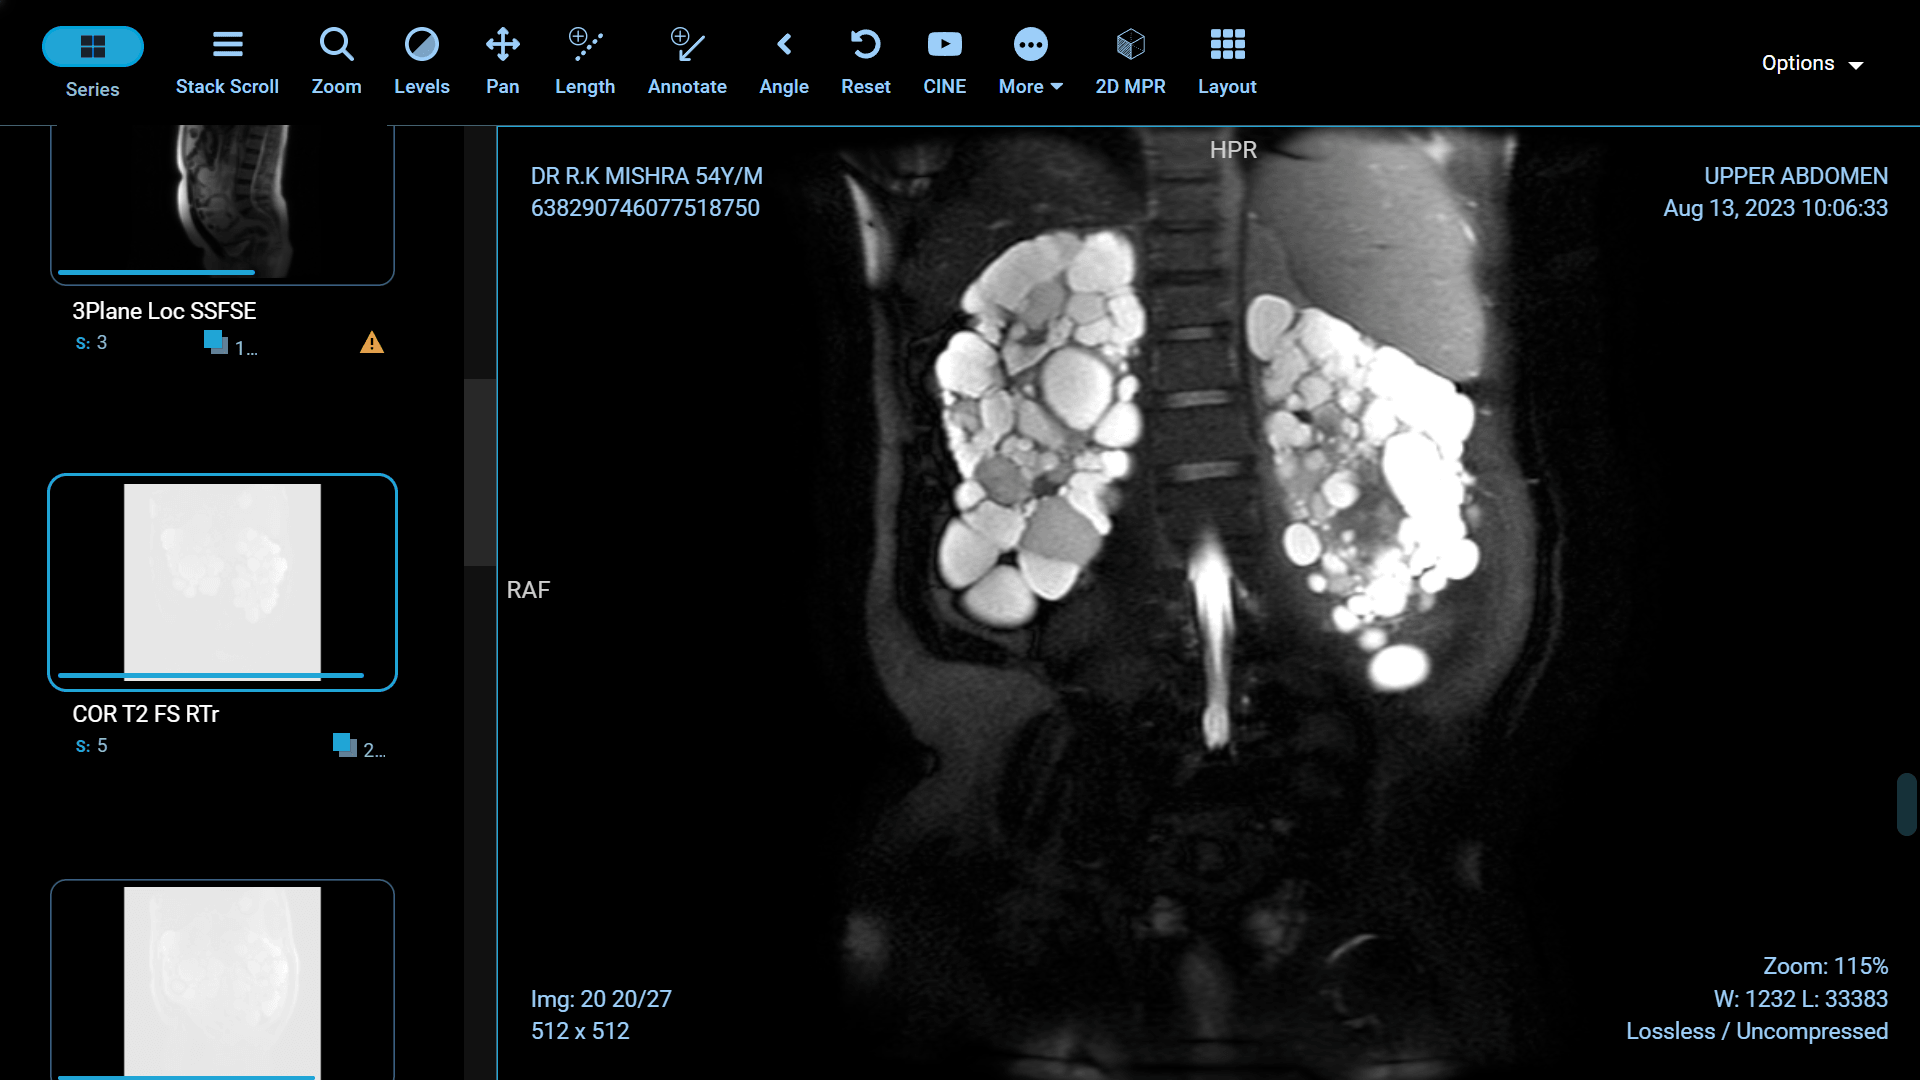

Polycystic Kidney Disease (PKD) is a genetic disorder characterized by the formation of fluid-filled cysts in the kidneys, which can lead to renal failure if left untreated. Fortunately, recent advancements in medical science have paved the way for more effective treatments and improved the quality of life for those affected by this condition. In this article, we will explore some of the groundbreaking innovations in PKD treatment.

Foam sclerotherapy is a medical procedure that involves injecting a specialized foam directly into kidney cysts. The foam is made by mixing a liquid sclerosing agent, typically a solution of alcohol or polidocanol, with air or gas to create a stable, persistent foam. This foam is then injected into the cyst through a thin needle under ultrasound or CT guidance.

The success of foam sclerotherapy lies in its ability to cause intentional injury to the cyst lining, promoting inflammation and scarring. This process leads to the collapse and sealing of the cyst, preventing further fluid accumulation and reducing the cyst's size.

Preservation of Healthy Kidney Tissue: Unlike some other treatments, foam sclerotherapy specifically targets the cyst, leaving the surrounding healthy kidney tissue intact. This is particularly important for individuals with only one functioning kidney.

Potential for Multiple Cysts: Foam sclerotherapy can be used to treat multiple cysts in one or both kidneys during a single procedure, reducing the need for multiple interventions.